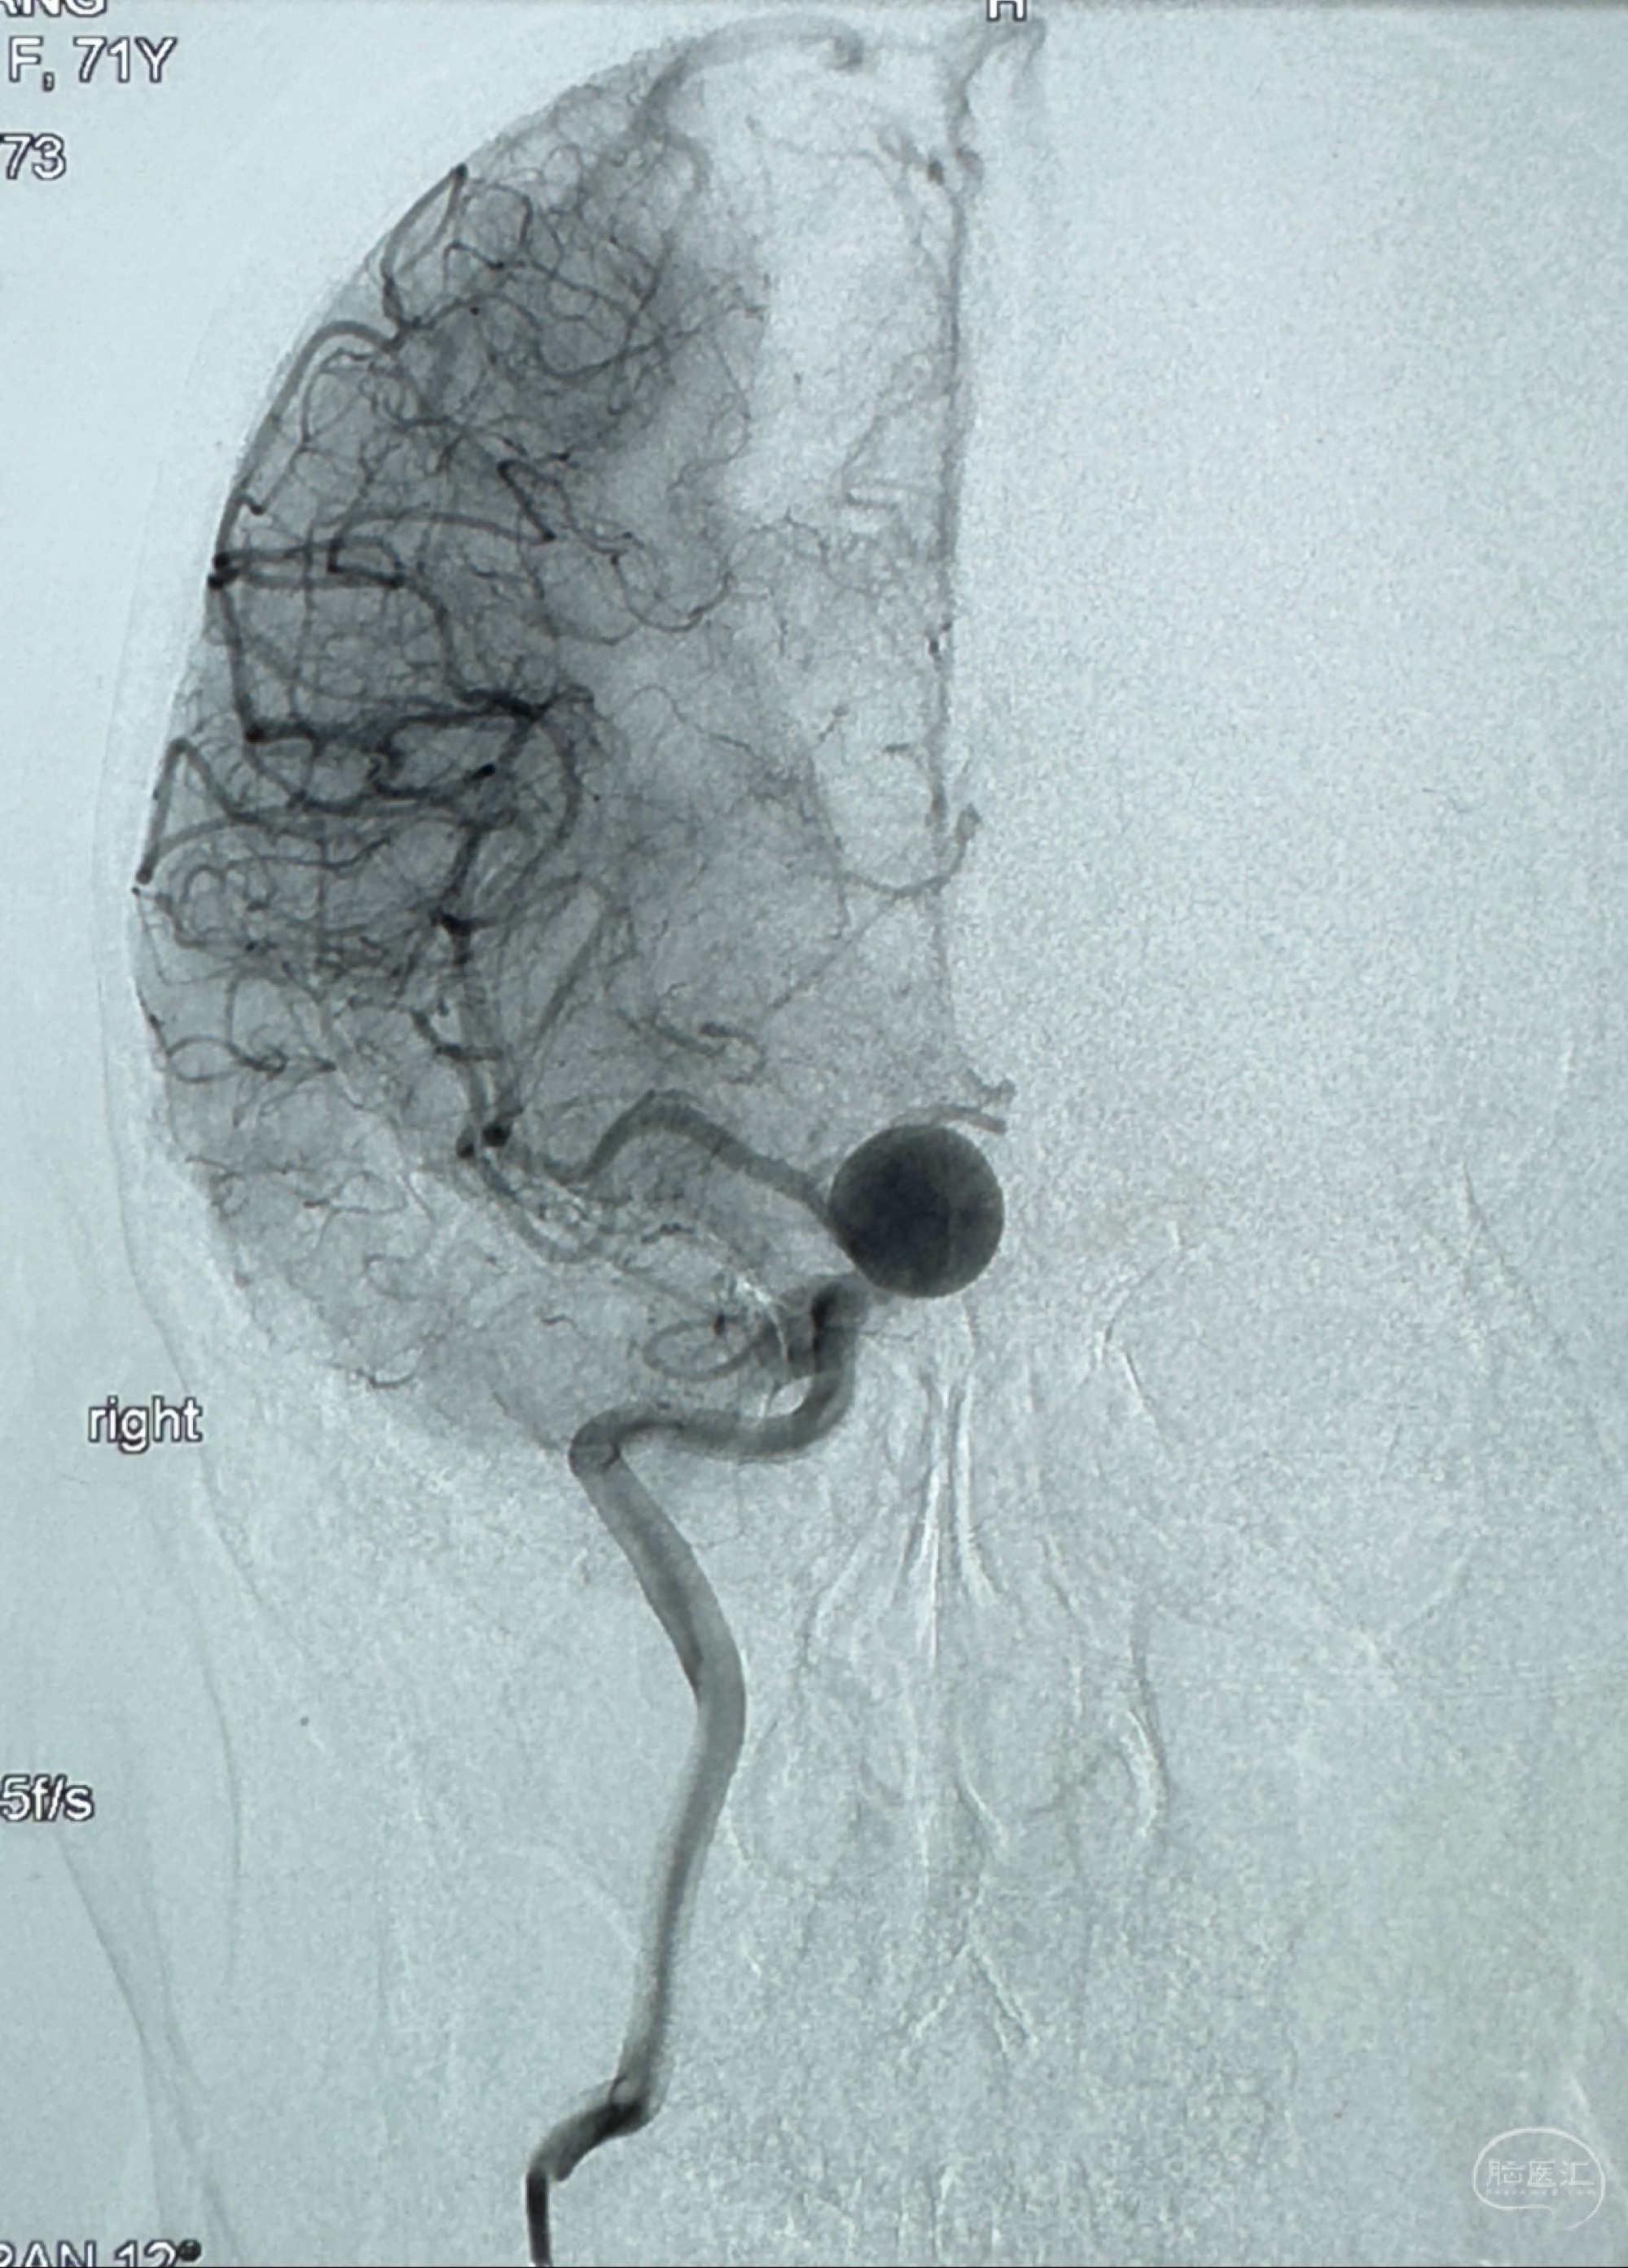

2023-12-08 复旦大学附属华山医院 全脑血管造影:右侧颈内动脉C6段动脉瘤,瘤颈6.68mm,动脉瘤大小13.28*12.34mm

2023-12-08外院DSA:右侧颈眼动脉瘤,约13*12mm大小,压颈试验显示左右向及后向前代偿可

测量动脉瘤的大小:16*13.8*7.6mm大小,较原先变大,考虑双抗后瘤内血栓溶解可能